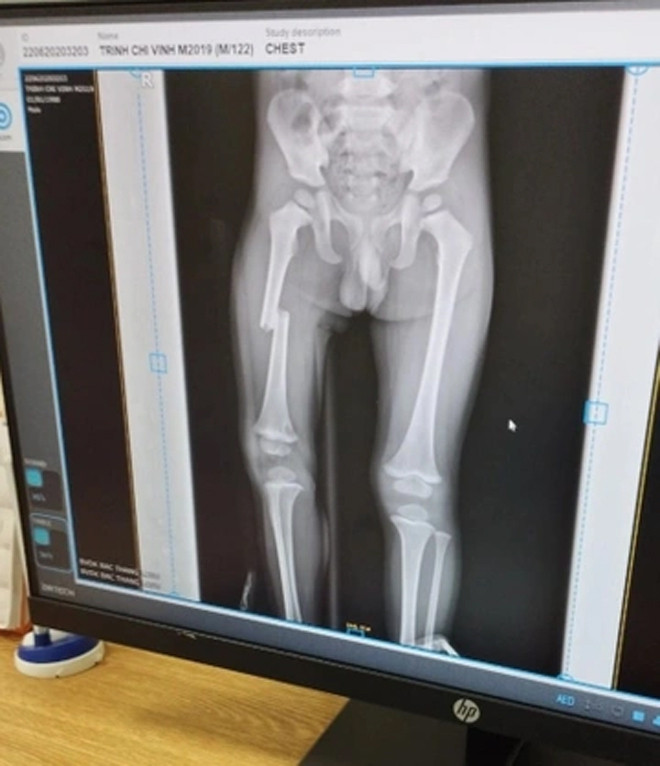

Ảnh chụp X-quang xương chân cháu bé. (Ảnh: Gia đình cung cấp).